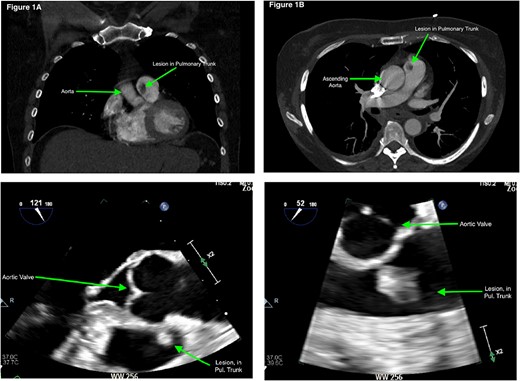

Acute coronary syndrome was excluded. A differential of pulmonary embolism (PE) was considered given the D-dimer was 5.4 mg/L. A computerized tomography of the pulmonary arteries (CTPA) was negative for PE but demonstrated a filling defect in the pulmonary trunk (PT) (Fig. 1a and b). The lesion was closely associated with the PV. Differentials included PV vegetation, thrombus, or cardiac tumour.

(a) and (b) Computerized tomography scan (coronal and axial slices) demonstrating filling defect in the pulmonary trunk. (c) and (d) TOE images of the PV lesion.

Blood and urine cultures were negative and inflammatory markers were normal. Transthoracic echocardiography (TTE) demonstrated a structurally and functionally normal heart with a mobile echogenic mass on the PV attached to the anterior leaflet. The PV looked morphologically and functionally normal. A transoesophageal echocardiogram (TOE) demonstrated a homogenous hyperechogenic and highly mobile mass on the PV measuring 10 × 13 mm on the anterior leaflet, concerning for a cardiac tumour, its appearance not suggestive of a clot or vegetation (see Video 1, Fig. 1c and d). Given the large size of the tumour urgent cardiothoracic review was sought and excision was recommended.